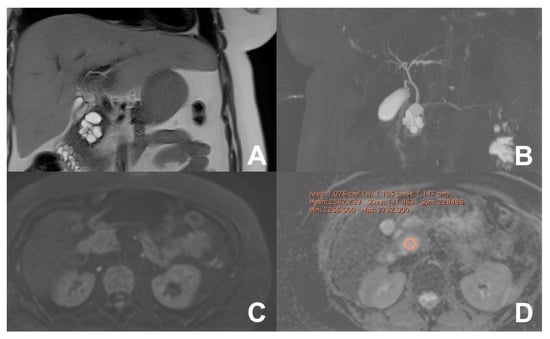

| Acute pancreatitis (AP) | HASTE T2 | AXIAL | -- | Anatomy and analysis of the content of collections |

| Indications: MRI is the technique of choice to detect biliary calculi either in the hepatic parenchyma or in the choledocus. It is useful to confirm/exclude biliary calculi in patients with AP. Moreover, MRI is able to better characterize the content of collections, thus allowing an appropriate management, either percutaneous/endoscopic or surgical. MRI can be used to follow-up AP in young and child-bearing patients. Finally, with DWI it is possible to better identify an infected collection. | HASTE T2 | CORONAL | -- | Anatomy and analysis of the content of collections |

| T1 GRE FS | AXIAL | -- | Pancreatic parenchima assessment | |

| DWI b 0–50–400–800 | AXIAL | -- | Infected collections appear hypointense in the ADC map | |

| GRE T1 3D DYNAMIC | AXIAL | Pre- 25″–70″–180″ | Not always necessary | |

| MRCP 3D/2D | OBLIQUE CORONAL | Anatomy of wirsung duct | ||